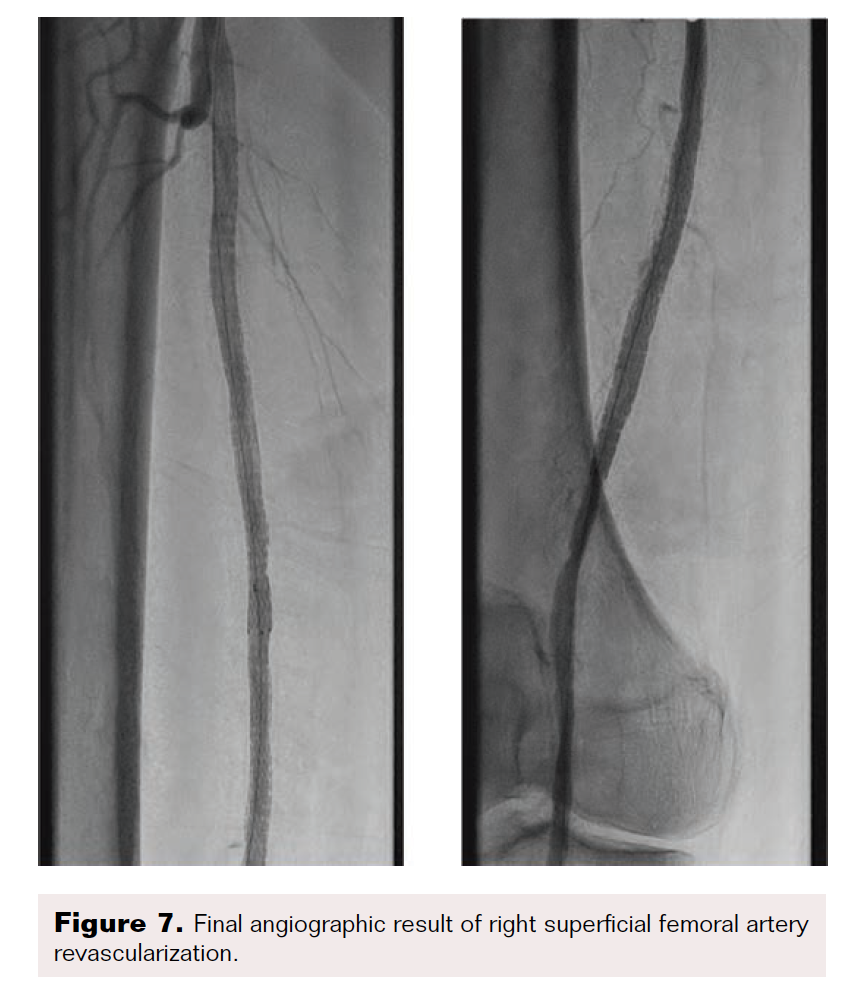

After the wire exchange, we attempted to aspirate, then flush, the 6F sheath with heparinized saline. After multiple failed attempts at sheath aspiration, we suspected a clotted arterial sheath and immediately proceeded to sheath exchange with a new 6F 45 cm sheath. Cautious to maintain wire position, the sheath was successfully exchanged. Saline flushing of the removed sheath resulted in expulsion of extensive clot burden (Figure 5). Repeat ACT confirmed therapeutic anticoagulation. The procedure concluded with percutaneous transluminal angioplasty followed by stenting of the SFA with BioMimics 6 x 150 mm stents (Figure 6). Final angiography demonstrated brisk flow through the SFA, popliteal, and anterior tibial arteries with no evidence of distal embolization (Figure 7 and Figure 8).